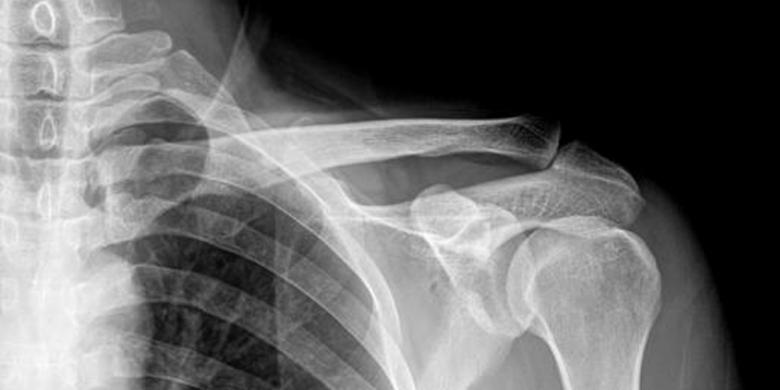

Berdasarkan berita yang dilansir laman UPI.com,

Rabu (6/4/2016), petugas perubatan menemui sebuah benda mirip cincin kahwin tersangkut di kerongkongannya. Penemuan ini diperoleh dari pemeriksaan

sinar x terhadap pelaku.